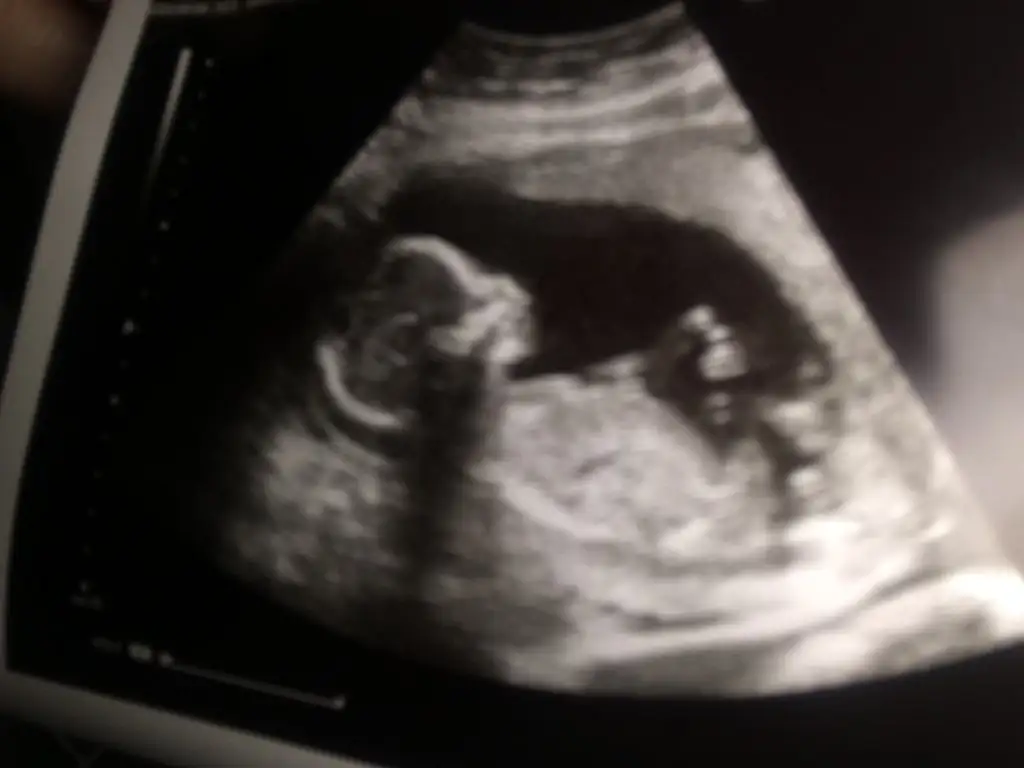

Erkek gibi geldi bana hayırlısıyla doğsun inşallah

6-9 Haftalardaki ultrason görüntüsü varsa gönder beni etiketle yorumlıyım canım burda büyük ben bu şekilde anlamıyorumBanada 12 de erkek 16 da kız dedi anlayan varmı ultrasondan

6-9 Haftalık ultrason görüntüsü yollarsanız bakayım böyle bilemiyorum maalesef nub anlamıyorumMerhaba banada bir tahminde bulunabilirmisiniz. Teşekkürler 15 haftalık Eki Görüntüle 3208672

Amin inşallah gönlümden geçen kızErkek gibi geldi bana hayırlısıyla doğsun inşallah